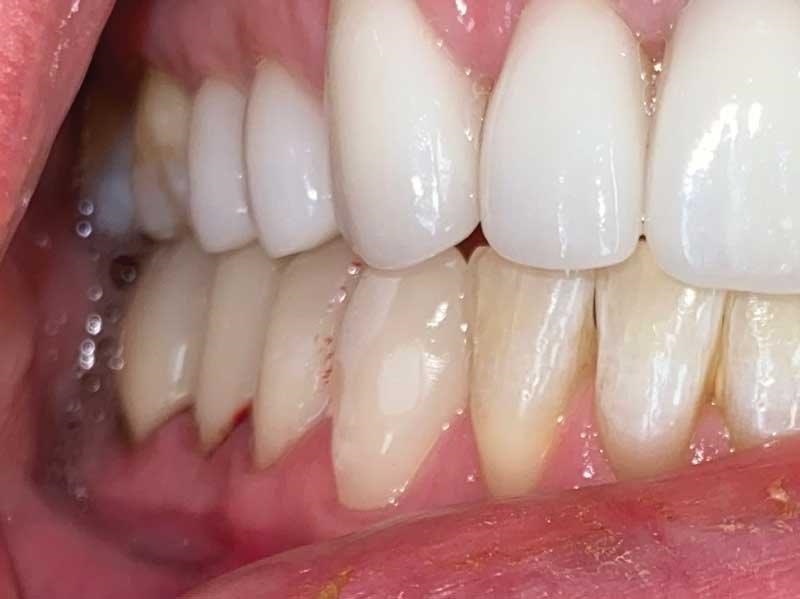

Lorraine drives six hours each way to see me, so I did her case all in one day: TENS bite; sectioned it; built up the lowers with resin to open the vertical (this is one of the cases I didn’t want to send out to a lab); prepped for 10 upper veneers (Fig. 24); temporized uppers; checked occlusion; and refined with TekScan. She came in with broken-down bonding and constant migraines, and left with beautiful temporaries and no more headaches. She came down a few weeks later to insert her gorgeous veneers (Fig. 25, thanks to Aurum Group) and I prepped, scanned, designed and milled and inserted her lower onlays to restore her lower teeth to her new vertical (Figs. 26–31). She has been pain-free ever since.

Dental Occlusion

Fig. 26

Fig. 27

Fig. 28

Fig. 29

Fig. 30

Fig. 31